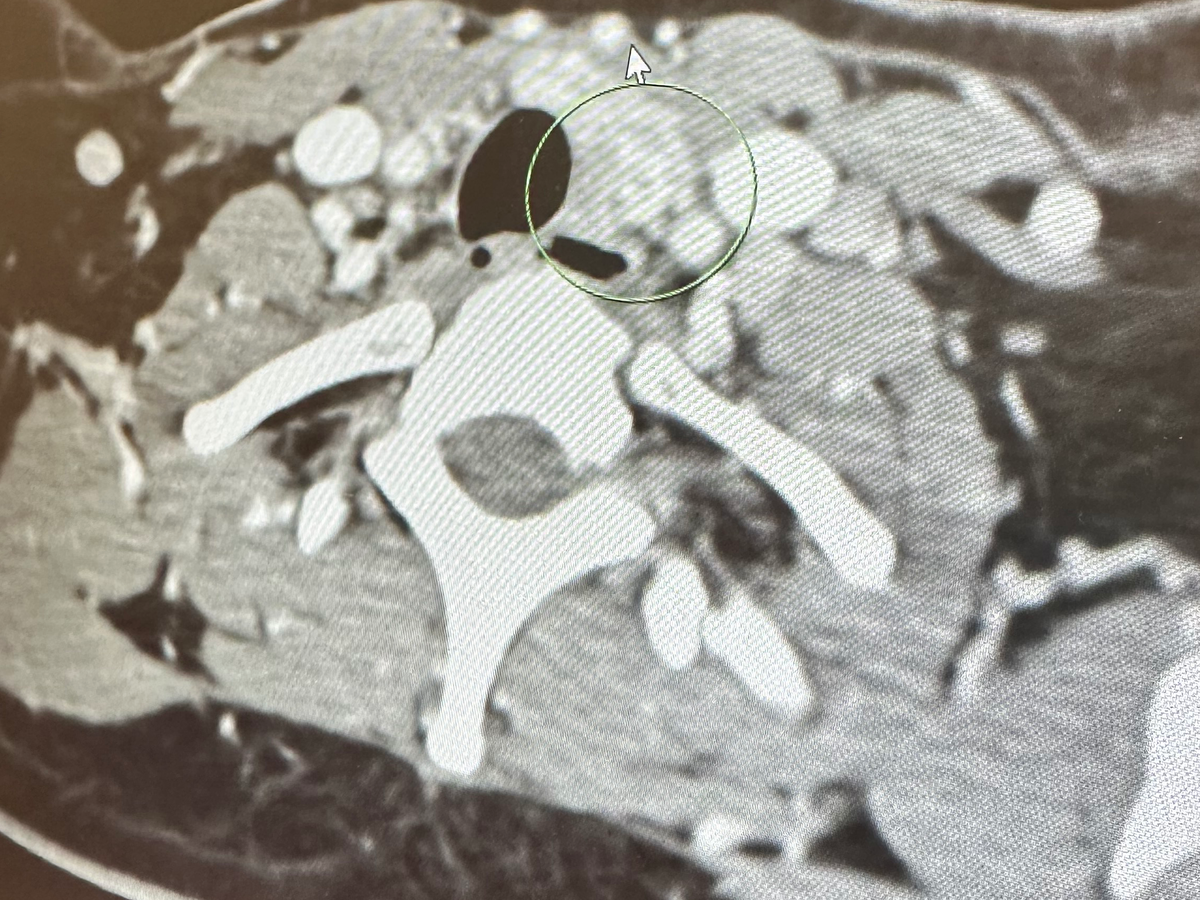

In January 2025, I was diagnosed with papillary thyroid cancer — a form of cancer that can spread to the lymph nodes and beyond. In April 2 days before my 30th, I underwent a total thyroidectomy and left neck dissection, where 34 lymph nodes were removed, and 12 tested positive for cancer. We originally thought it was only in the left lobe but it ended up being spread throughout both sides of the whole thyroid too.

Shortly after, I received the devastating news that I have not just papillary thyroid cancer — but a rare and aggressive variant called Diffuse Sclerosing Variant Papillary Thyroid Carcinoma (DSVPTC) Extensive lymphovascular

invasion identified ( the cancer has spread significantly into my small blood vessels and lymph node vessels in multiple spots)

making it very high risk and likely to have recurrence

In June, I underwent Radioactive Iodine Therapy (RAI), but follow-up scans revealed two remaining lymph nodes — one behind my left collarbone and one in my chest (mediastinum) — that are still cancer-positive. These will need to be monitored closely moving forward.